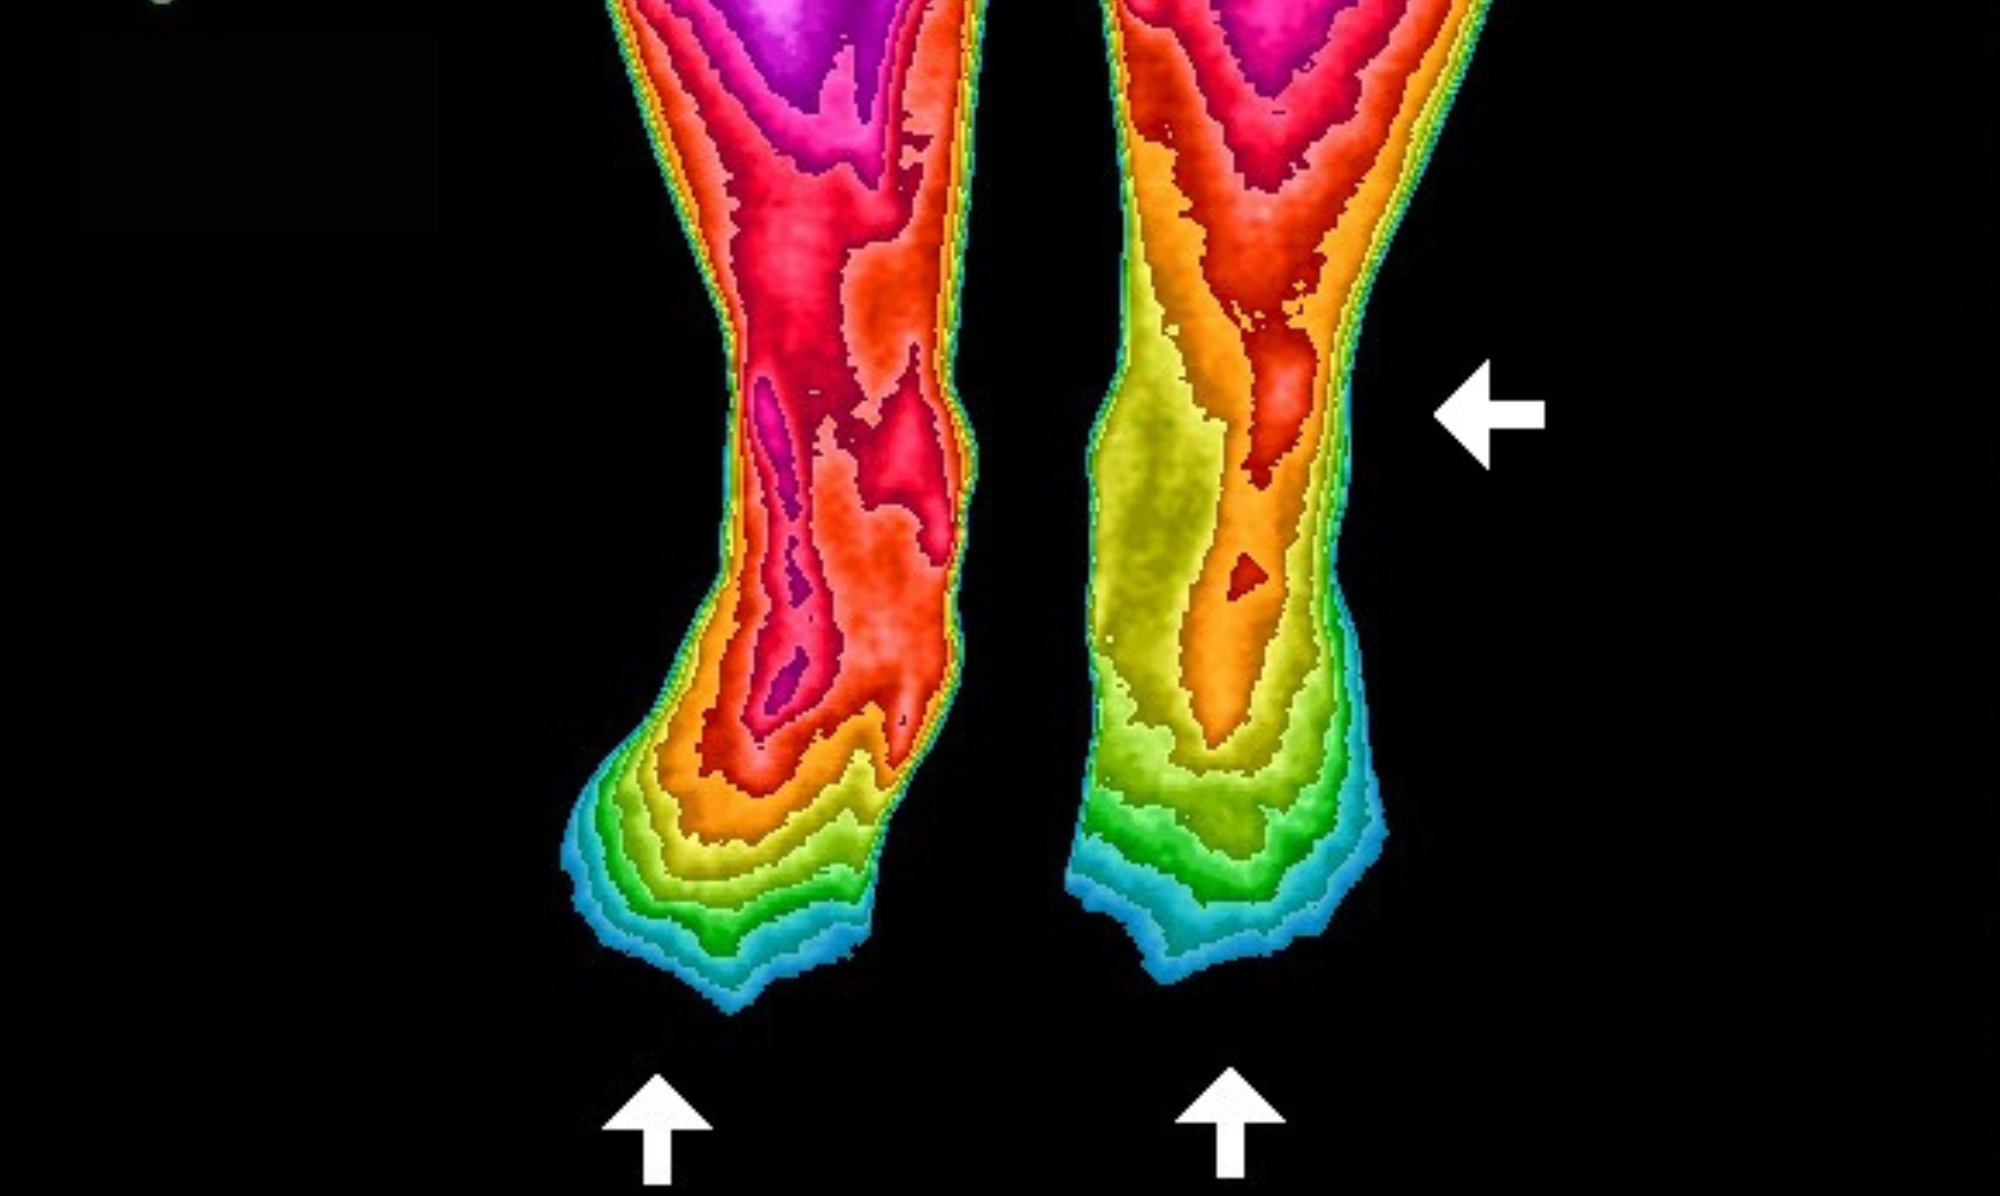

Earthing has been involved with more than 26 scientific studies showing how being grounded positively influences our bodies. These infrared images are an evaluation tool showing changes in blood flow before and after grounding for two weeks on our Ground Therapy Mattress Cover. Before grounding, circulation was almost non-existent in the toes. After grounding, normal circulation has been restored. This is one small example of the studies that have been done.